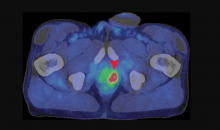

Yael Eshet, M.D., MSc, a diagnostic radiology specialist at Sheba Medical Center in Israel, was the lead author on a recent study that showed COVID-19 (SARS-CoV-2) vaccine adenopathy can persist more than 6 weeks. This swelling of lymph nodes is similar to what is seen cancer and infections and the new findings show it can last longer than 7-10 weeks. The current recommended time people should delay medical imaging is 6 weeks after receiving a COVID vaccine to avoid a misdiagnosis,[2] but this new study shows there is increased inflammation shown on PET-CT imaging for much longer.

These were the findings in the Radiology published study "Prevalence of Increased FDG PET/CT Axillary Lymph Node Uptake Beyond 6 Weeks after mRNA COVID-19 Vaccination."[1]

Researchers using fluorodeoxyglucose (FDG)-positron emission tomography (PET) have found increased FDG uptake in the lymph nodes of patients 7-10 weeks past their second mRNA-based Pfizer-BioNTech COVID-19 vaccination. This new information indicates a persistent immune response that could be mistaken on imaging exams for serious conditions like lymphoma over a much longer period of time.

Recent recommendations for post-vaccine lymphadenopathy advise scheduling routine imaging, such as screening mammography, before, or at least 6 weeks after, the final vaccination dose to eliminate false positive results. However, this new research showed that avid axillary lymph node uptake was present beyond 6 weeks after the second vaccination in more than 29% of the patients in the study cohort.

The authors stated “This study shows that avid axillary lymph node uptake on FDG PET/CT can be detected in more than a quarter of our patient population even beyond 6 weeks after the second dose of the mRNA-based COVID-19 vaccination. Compared to a previous study showing normalization of FDG uptake within 40 days of receiving an inactivated H1N1 influenza vaccine, we found uptake persistence even at 70 days. Physicians should be aware of this potential pitfall.”

Some images in this video are from another Radiology study, which showed PET tracer uptake at the COVID vaccine injection site and other examples of axillary adenopathy.[3]